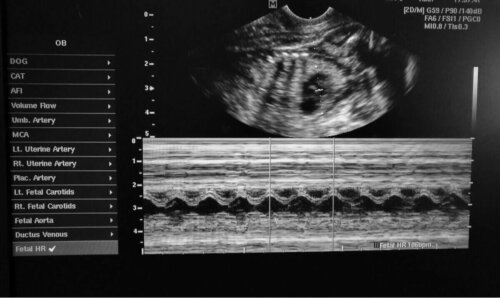

Den 6. februar 2021 blev en kyklop hund født på Filippinerne (Aklan), som det blev rapporteret af den digitale avis TimesNoNews. Dyrets mor fødte to hvalpe. En af dem var helt normal, og den anden havde den allerede nævnte cefale mutation. Som du nok kan forestille dig, var udsigterne for den lille kyklop ikke særlig lovende.

Hvalpens fremtoning kunne ikke have været mere atypisk. Denne hund var lille med en hvid pels og havde et kæmpe øje i panden og to store tunger, der stak ud fra hver side af munden. Da øjet optog så meget plads, havde hundens cefale struktur ingen næse eller snude.

Uheldigvis havde denne hund store problemer med vejrtrækningen fra det øjeblik, den blev født. Da den ikke var i stand til at klare sig selv, tog hundens ejer den med til dyrlæge i håb om, at den ville klare den med den rette behandling. Som forventet døde hunden til sidst omkring klokken 22 den samme dag på grund af vejrtrækningsproblemer.